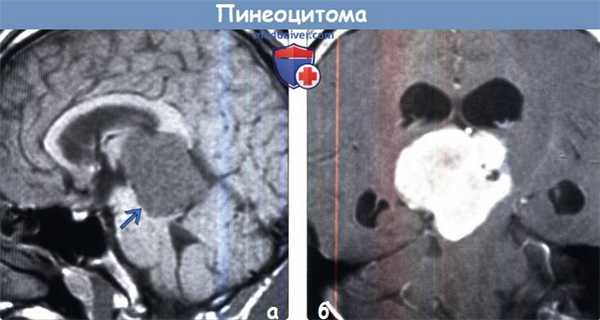

(а) МРТ, постконтрастное Т1-ВИ, аксиальный срез: в пинеальной области определяется объемное образование дольчатой, частично кистозной структуры, частично накапливающее контраст. Среди опухолей паренхимы эпифиза пинеоцитома встречается наиболее часто. При кистозном строении эти опухоли могут имитировать доброкачественную пинеальную кисту.

(б) МРТ, постконтрастное Т1-ВИ, ко-рональный срез: у пациента с пинеоцитомой определяется как периферический, так и более солидный характер контрастирования кистозного пинеального объемного образования. Также присутствует мелкий центральный очаг контрастирования по типу мишени.

(а) МРТ, Т1-ВИ, сагиттальный срез: определяется вариант структуры пинеоцитомы. Присутствует крупная дольчатая опухоль, четко отграниченная от окружающих тканей, которая вызывает обструктивную гидроцефалию вследствие компрессии сильвиева водопровода. Опухоль слегка гиперинтенсивна по отношению к СМЖ и умеренно гипоинтенсивна по отношению к ткани мозга.

(б) МРТ, постконтрастное Т1-ВИ, корональный срез: определяется выраженное контрастирование опухоли с умеренно гетерогенным его характером. «Вариантные» случаи предполагаемой пинеоцитомы необходимо дифференцировать с ОПЭПД, более агрессивной опухолью.